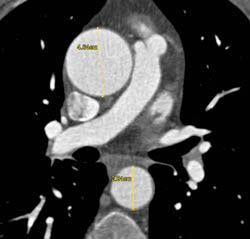

Diseased Leaflet Aortic Valve